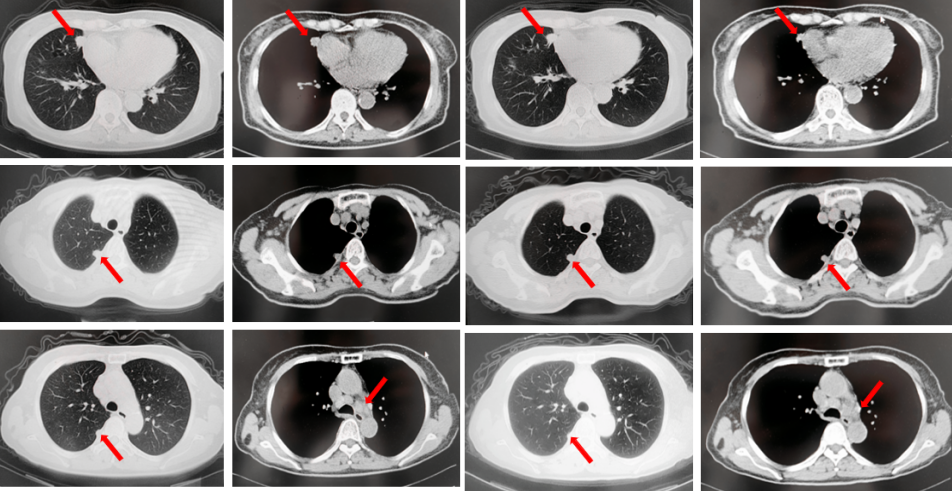

67岁女性患者,无既往病史。2019年10月患者因右侧季肋部不适行肺CT提示右肺中叶改变,双肺结节,右侧胸腔积液。行右侧胸腔穿刺引流,送检胸腔积液,液基薄层结果提示肺腺癌。确诊为右肺中叶恶性肿瘤cT2bN1M1a IVA期。基因检测(胸腔积液):EGFR L858R突变。建议患者口服奥希替尼,患者拒绝。2019年11月始口服埃克替尼,定期复查,最佳评效PR(图5)。

图5:A.第2例患者的基线影像资料,由上至下依次为右肺肿物、双肺转移灶及右侧胸腔积液;B.EGFR-TKI一线治疗后最佳复查评效,肺内病灶较前缩小,胸腔积液较前明显吸收。

2020年11月复查评效PD。复测基因检测(血检):T790M阳性,改行奥希替尼治疗,期间评效均为SD(图6)。

图6:A.埃克替尼靶向治疗后病情进展,肺内病灶较前增大,右肺近胸膜处新发转移灶;B.更换三代EGFR-TKI治疗后复查多处病灶未见明显变化。